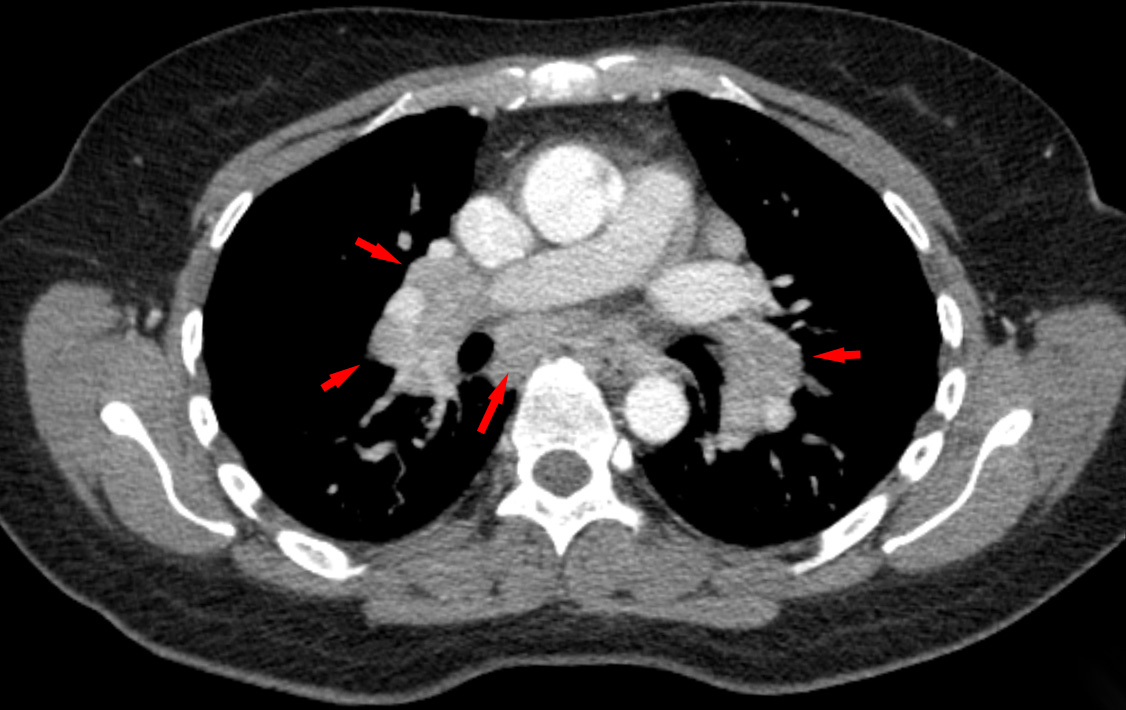

The granulomas mostly affect the hilar lymph nodes and lungs, causing restrictive lung disease.

Histology of sarcoidosis includes naked granulomas and stellate inclusions (‘asteroid bodies’) are often seen within giant cells of the granulomas.